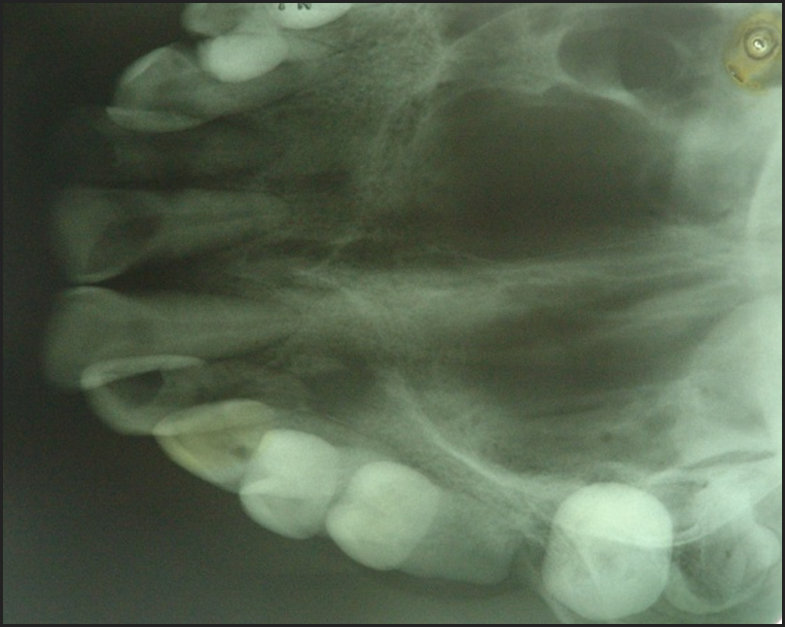

Based on anamnesis and clinical examination, we made the differential diagnosis of common lesions in the soft tissues of the oral cavity: Pyogenic Granuloma, Peripheral Lesion of Giant Cells, Traumatic Fibroma and Peripheral Ossifying Fibroma. Periapical and occlusal radiographic examinations were performed where we did not detect any type of bone alteration. (Figure 3)